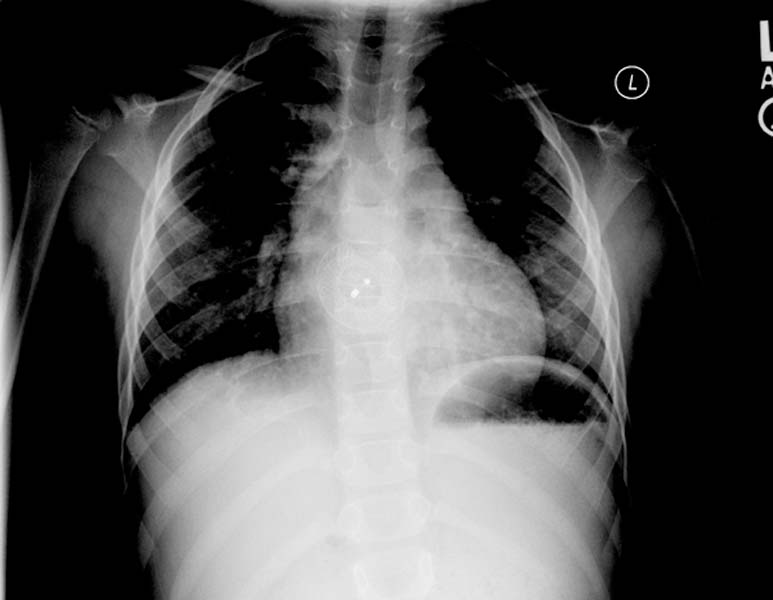

Декстрокардия

Декстрокардия 116 фото